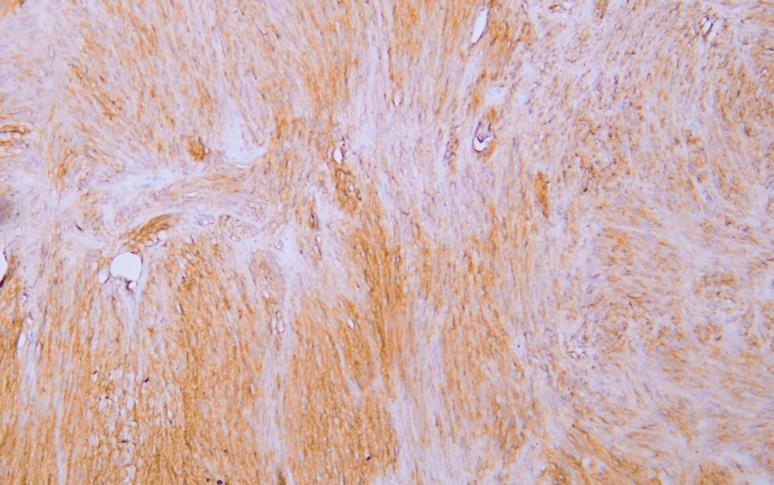

CD117 (C-kit) (AB1257) mouse mAb

Application:Immunohistochemistry (IHC)

CD117 is a cell membrane protein encoded by the c-kit proto-oncogene and is a type III transmembrane protein tyrosine kinase growth factor receptor. CD117 is expressed in mast cells, melanocytes and interstitial cells of Cajal. CD117 is positive in 80-100% of gastric stromal sarcoma (GIST) . CD117, as a specific marker for immunohistochemical examination of gastric stromal sarcoma (GIST) , can be used to clinically guide the personalized target drug (Gleevec) treatment of GIST patients. CD117 can also be used to identify mast cell tumors in lymphoma and as a marker for some testicular germ cell tumors.

Immunohistochemistry (IHC)

IHC, 1:50-1:200